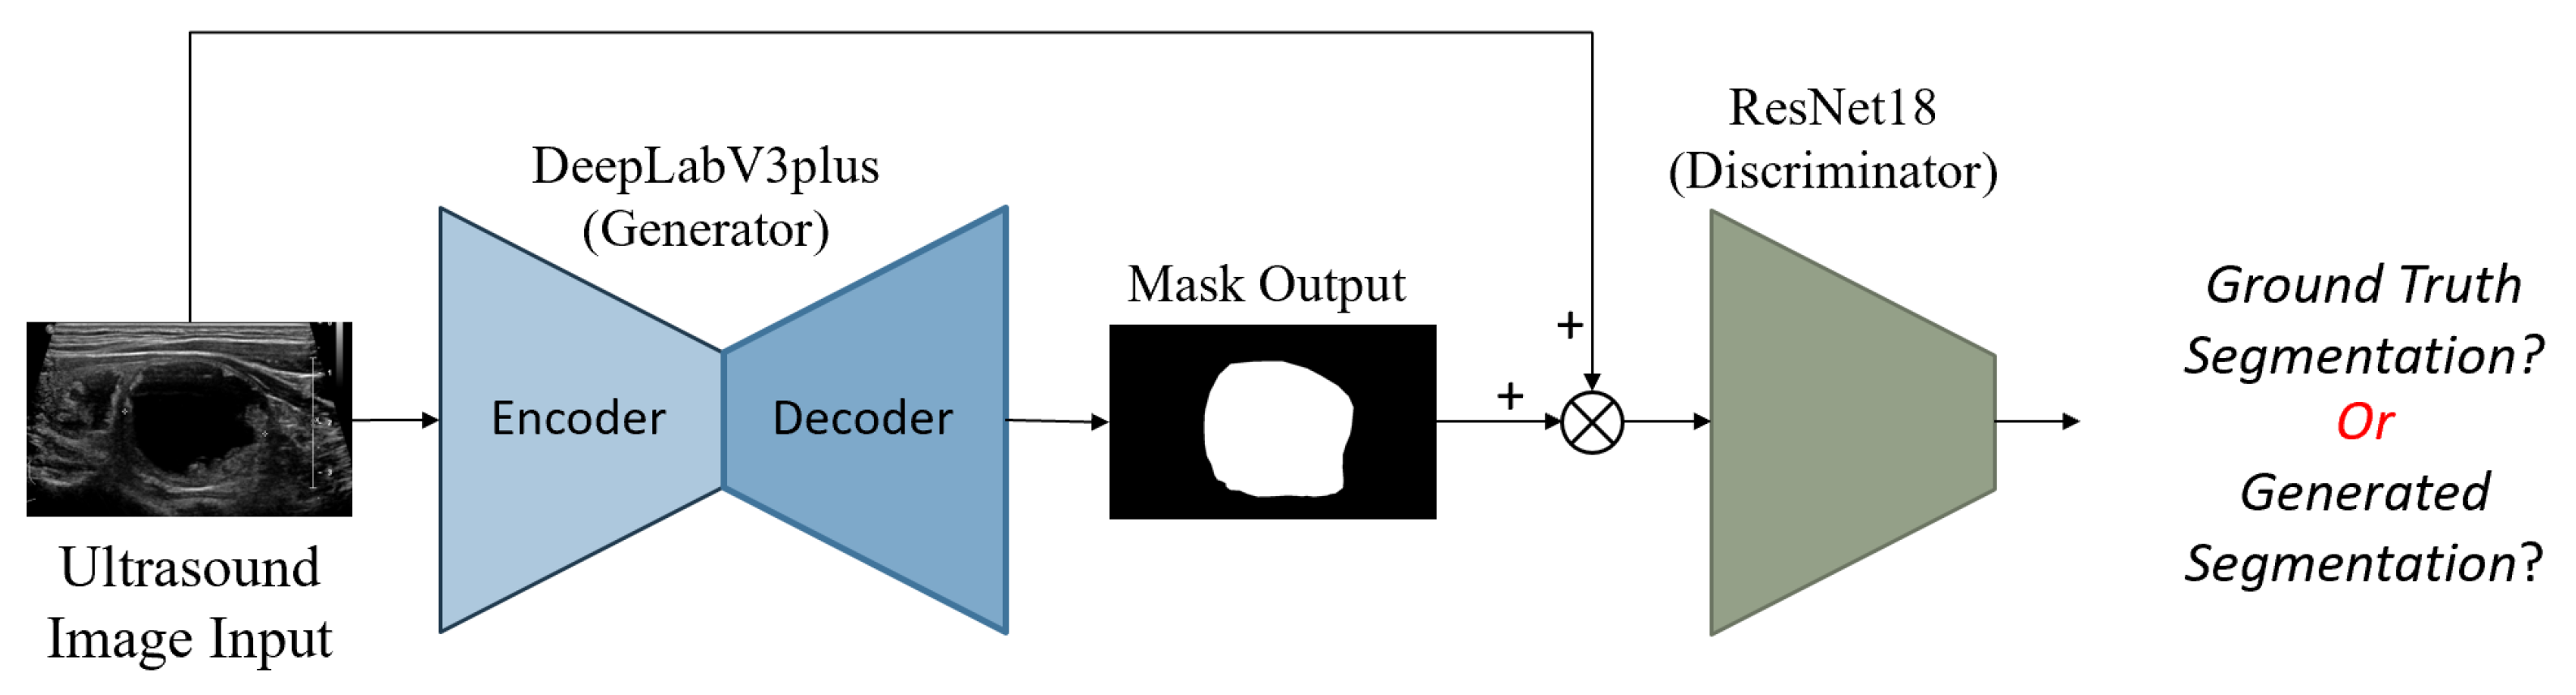

3.3. Input Images and Multiple Output Classification

Ultrasound images are typically grayscale, but they can be combined with other image types as input to a neural network. Multiple tensors of images can be used to convey different information, such as segmenting nodules to indicate their position. In this paper, we provide three tensors of images: an ultrasound image, a sharpened version of the ultrasound image (enhanced using 3 × 3 max-pooling with stride 1 to reveal micro-calcifications more clearly), and a segmented nodule image to concentrate the model on the nodule. The segmentation is implemented by StableSeg GANs [

24], as shown in detail in

Figure 5. Previous research has utilized ResNet and DenseNet to classify thyroid nodule ultrasound images as benign or malignant. However, no models have been designed for the multiple fine-grained classifications required by TI-RADS. To address this, we modified the ResNet50 and DenseNet201 classification models from a single output layer to multiple outputs, including TI-RADS types such as composition, echogenicity, margin, and echogenic foci. The model can easily calculate the shape of the nodule from the segmented nodule image, eliminating the need for the deep learning model to learn to predict the nodule’s size.

Figure 6 shows the overall input and output of the model.

Figure 5.

StableSeg GANs. This GANs-based segmentation model utilizes DeepLabV3+ as a generator and ResNet16 as a discriminator. Reprinted from Kunapinun et al. [

24].

Figure 5.

StableSeg GANs. This GANs-based segmentation model utilizes DeepLabV3+ as a generator and ResNet16 as a discriminator. Reprinted from Kunapinun et al. [

24].

Figure 6.

Overall input and output of the model, illustrating the integration of different image tensors and the multiple classification outputs for TI-RADS.

Figure 6.

Overall input and output of the model, illustrating the integration of different image tensors and the multiple classification outputs for TI-RADS.